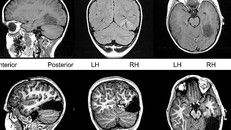

Tanner bị cắt bỏ 1/6 não bộ để ngăn ngừa chứng động kinh. (Ảnh: Dailymail).

(Ngày Nay) -Cậu bé Tanner Collins phải cắt bỏ 15% bộ não để ngăn chặn những cơn động kinh khó chữa.